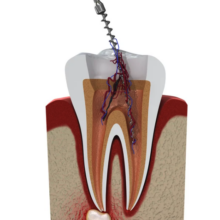

Procedimento que elimina infecções e preserva dentes comprometidos, aliviando a dor e evitando extrações.

Endodontista